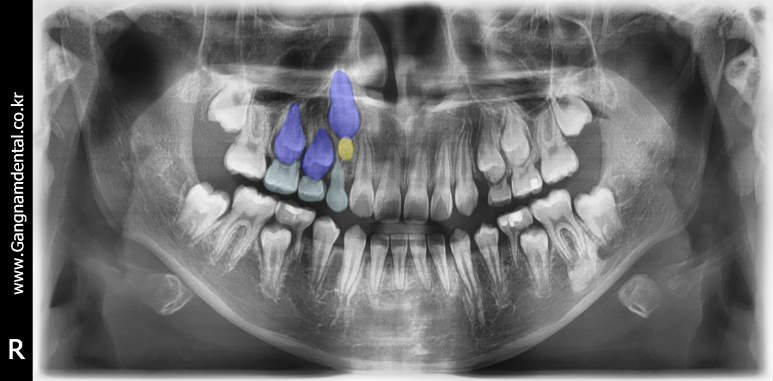

소아 매복과잉치 (하늘색:유치/파란색:영구치/노란색:과잉치) - 과잉치(노란색)가 영구치(파란색)의 맹출을 방해하고 있다.